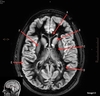

Image weighting and axis

T2 Axial

A

Caudate Nucleus

B

Thalamus

C

Third ventricle

D

Lentiform Nucleus

E

Frontal Sinus